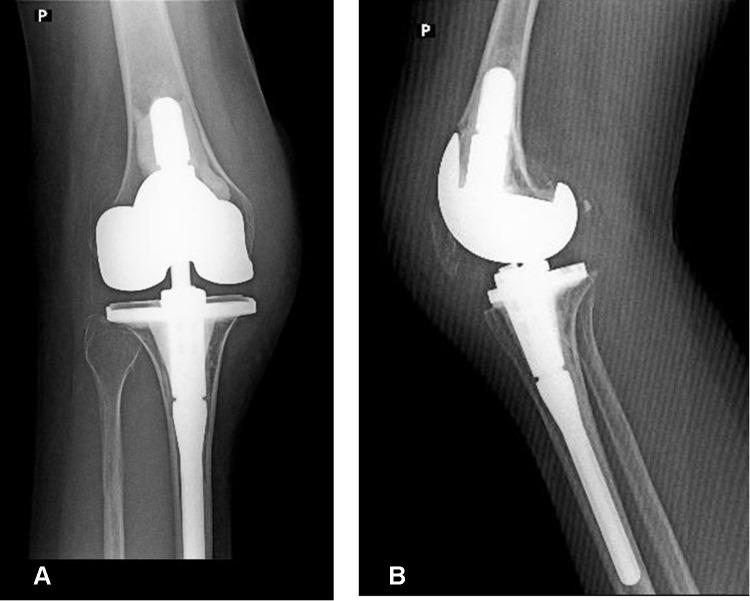

A 49-year old woman with a history of spondyloepiphyseal dysplasia suffered from severe osteoarthritis of the knee and irreducible congenital dislocation of the patella. After careful preoperative evaluations and planning, the knee joint deformity was solved by knee joint replacement with realignment of the extensor mechanism using quadricepsplasty. After 2 years of surgery, the patient showed no pain and was able to walk with the help of elbow crutches. The Hospital for Special Surgery knee score increased from preoperative 51 points to 85 points during the final follow-up. The postoperative range of motion increased to final flexion of 0-115°.

一名49岁患有脊椎骨骺发育不良的女性,患有严重的膝关节骨关节炎和不可复位的先天性髌骨脱位。经过仔细的术前评估和规划,通过膝关节置换术并采用股四头肌成形术重新调整伸肌机制,解决了膝关节畸形问题。术后2年,患者无疼痛,能够借助肘拐行走。在最后一次随访时,特种外科医院膝关节评分从术前的51分提高到85分。术后活动范围增加到最终屈曲0 - 115°。